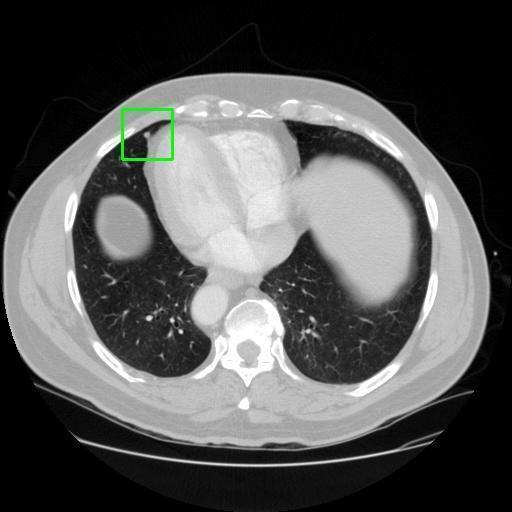

We developed an AI-based system using deep learning models for analyzing lung CT scans to detect and classify pulmonary nodules. We chose the YOLOv11 architecture for its enhanced object detection capability and adapted it specifically for medical imaging, incorporating pixel-level precision and severity classification.

Classification into three severity levels with colored bounding boxes.

Distinguishing between similar-looking benign and malignant nodules posed classification difficulty.

Designed a severity classification system that categorizes nodules into null, moderate, and severe using colored bounding boxes, assisting in rapid clinical decision-making.